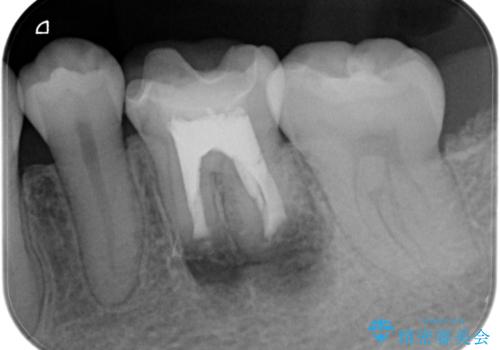

- 昔他院で根管治療を行った歯の病気が再発したことを主訴に来院されました。

レントゲンにて根尖に病変を認め、根尖性歯周炎の診断のもと以下の治療をご提案しました。

1、再根管治療を行い、3ヶ月以上経過を待ち、治癒しなければ外科的歯内療法を行う。

2、外科的歯内療法を行う。

以前の根管治療の質が不明なこと、補綴処置のやりかえにメリットがあることから、1の選択肢をお勧めしましたが、費用対効果の面を患者様と相談し今回は外科的歯内療法で治療することとしました。